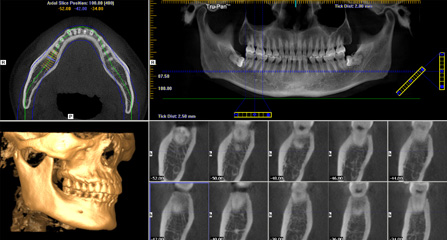

福能海峡口腔着眼于全链条的数字化诊疗解决方案,与德国ICX、瑞典Nobel、韩国奥齿泰等国际知名齿科品牌合作,建立“福州数字化口腔联盟”,应用全数字化口腔模式,从CBCT数据提取、AI口扫取模、AI智能口腔体检、数字化分析模拟与方案设计、3D打印、CAD/CAM椅旁加工以及手术模拟导航等,全流程打通数字化口腔精确诊疗的各个环节,实现福能海峡数字化口腔诊疗体系新升级。

• 三维影像数据 准确采集数据

智能口扫取模 避免数据误差

AI智能体检 时刻掌握牙齿健康状况

数据云端整合 智能方案模拟

• 3D可视呈现 医患无缝沟通

云端3D打印 导板辅助

动态导航监测 精确控制植入路径